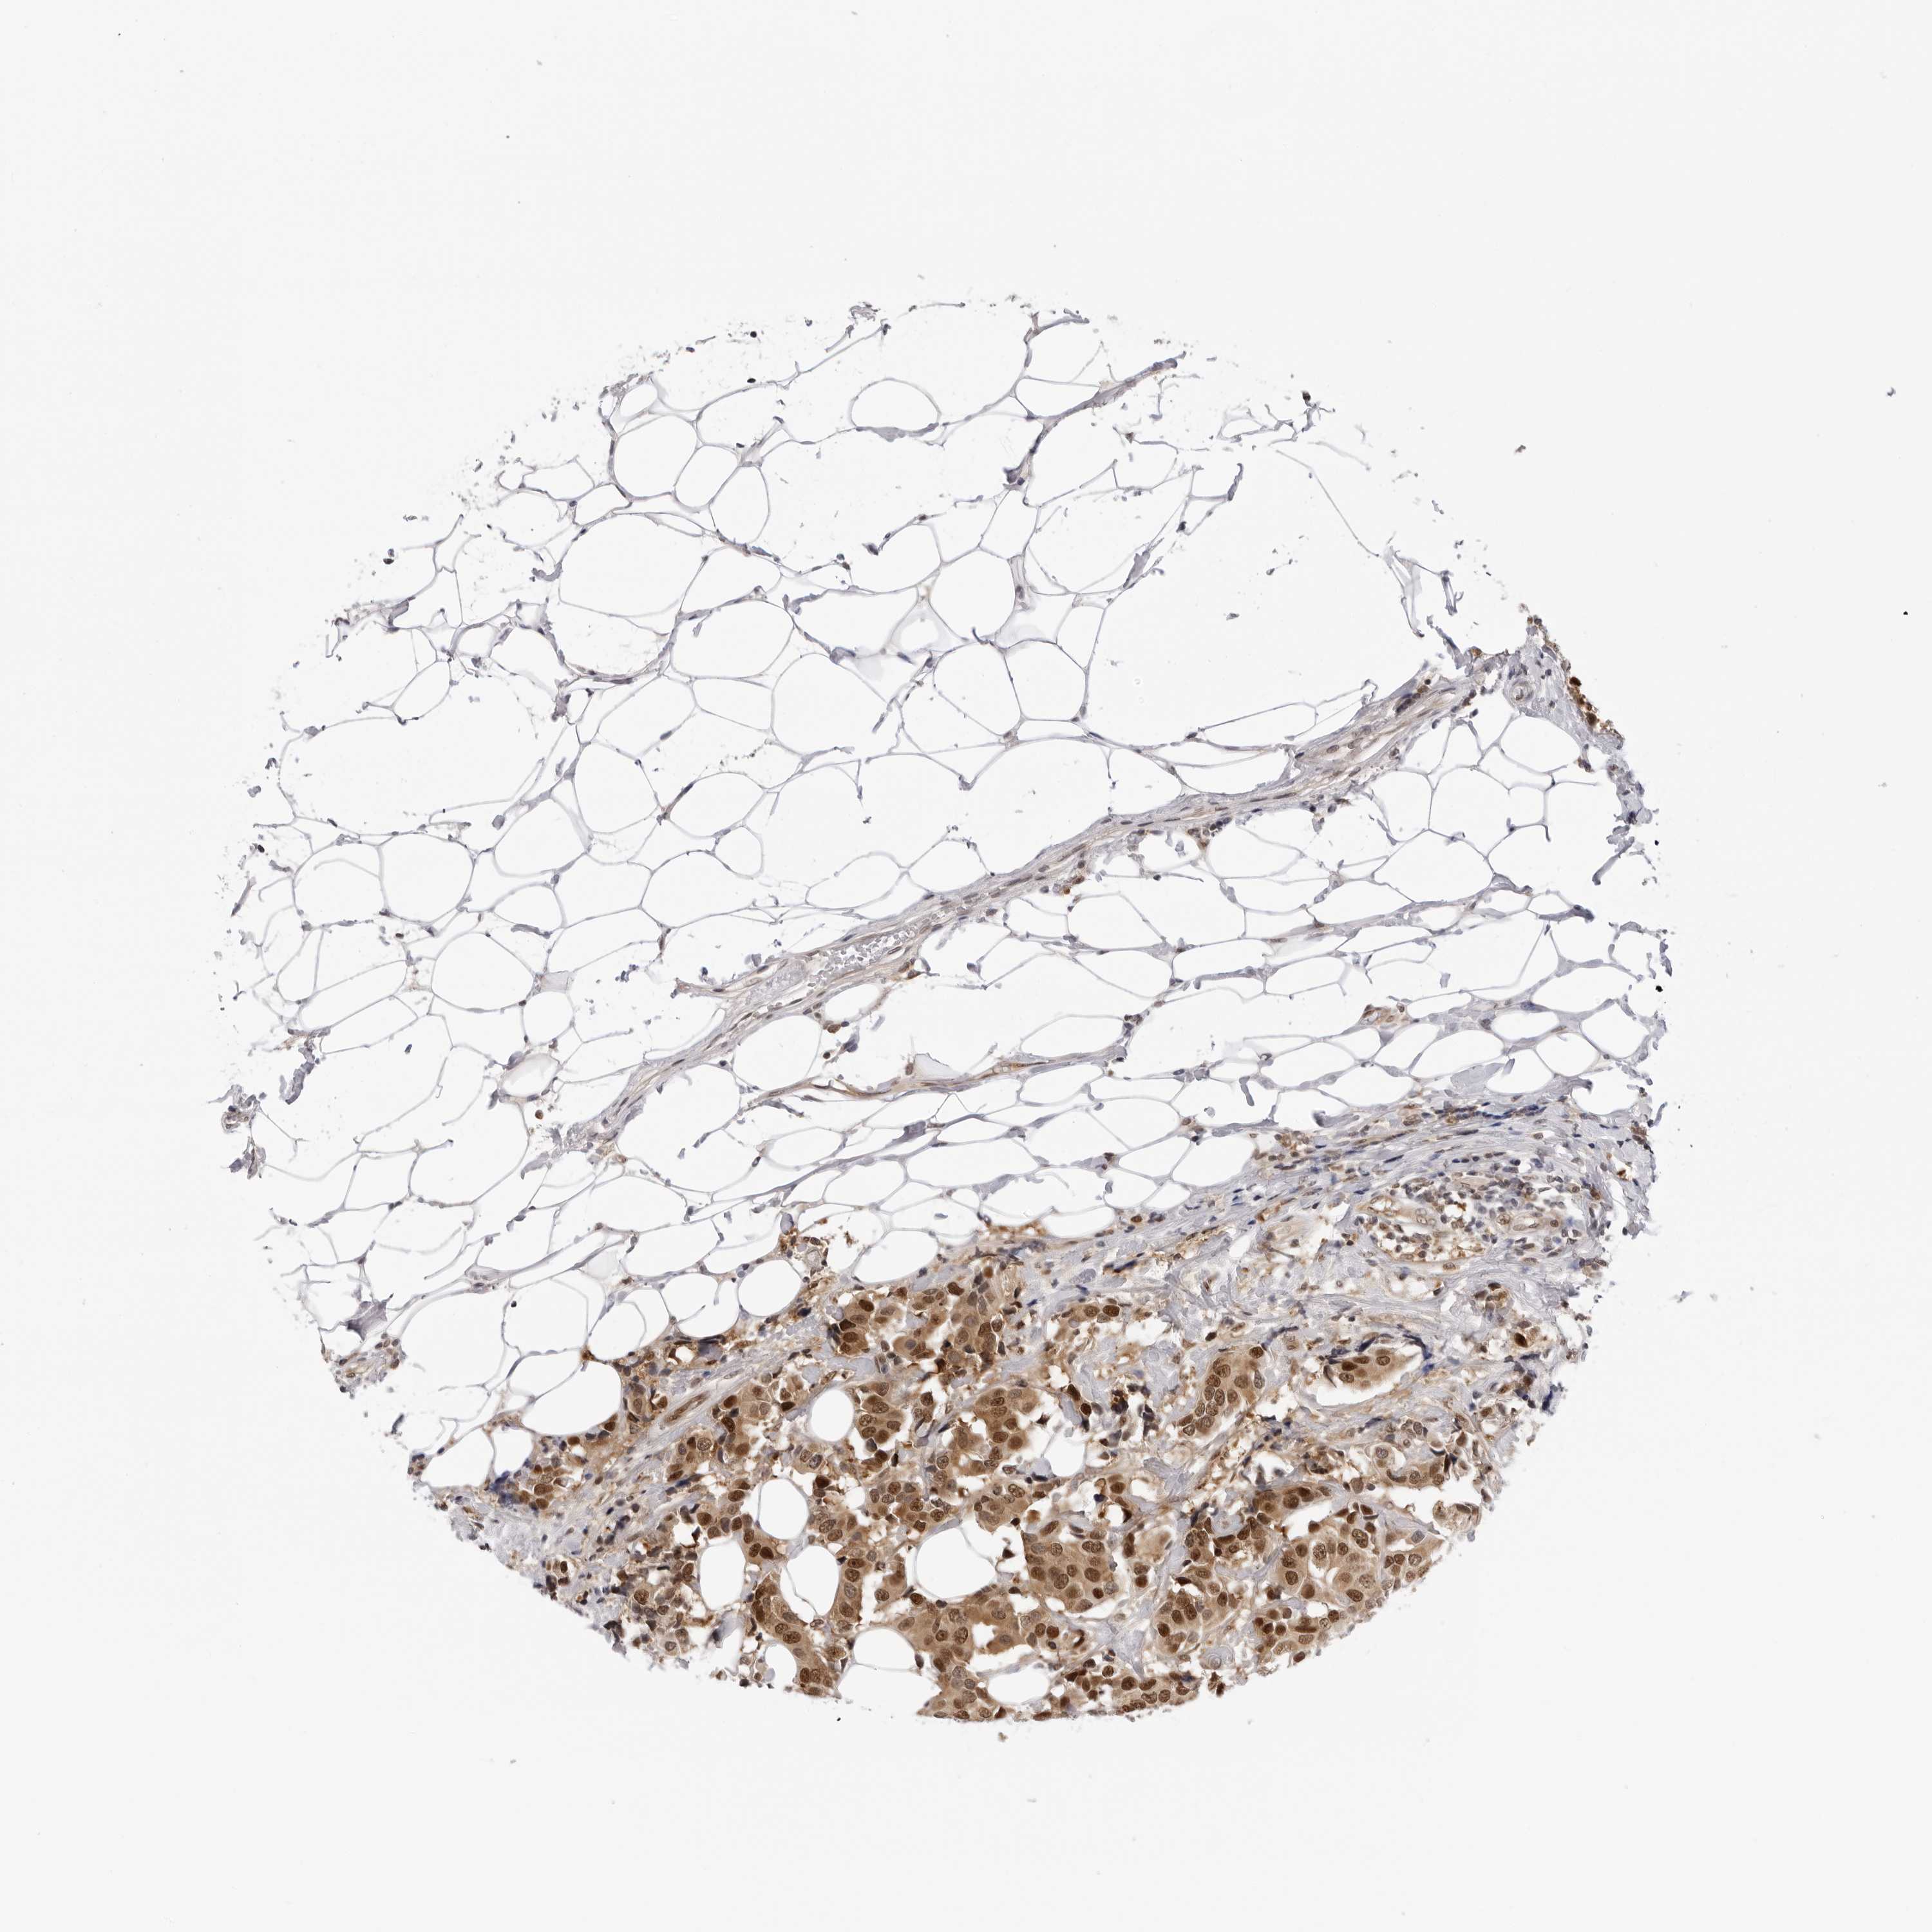

CANCER BREAST CANCER Show tissue menu

BRCA TCGA BRCA VALIDATION PROTEIN EXPRESSION